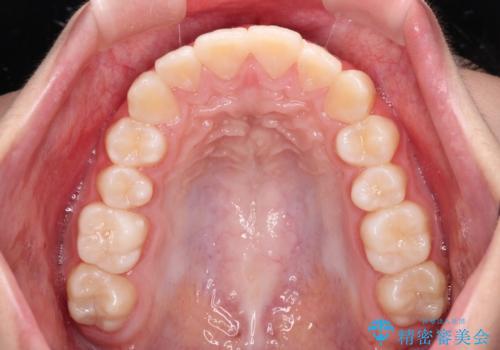

気がつくと唇があいてしまう ワイヤー装置での抜歯矯正

- 口元の突出感で口が閉じにくいとのことで来院された患者様です。

上下左右の第一小臼歯4本を抜歯し、ワイヤー装置での抜歯矯正を行うこととしました。

口元の突出感が解消され、睡眠時の口呼吸が改善されました。